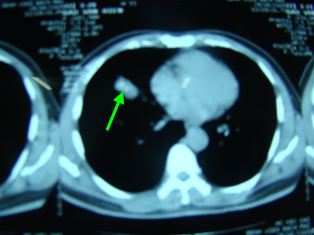

Chụp cắt lớp vi tính lồng ngực

Trước điều trị: Hình ảnh khối u thuỳ phổi phải, kích thước 26x13mm

Sau điều trị: Không còn khối u, không có hạch trung thất